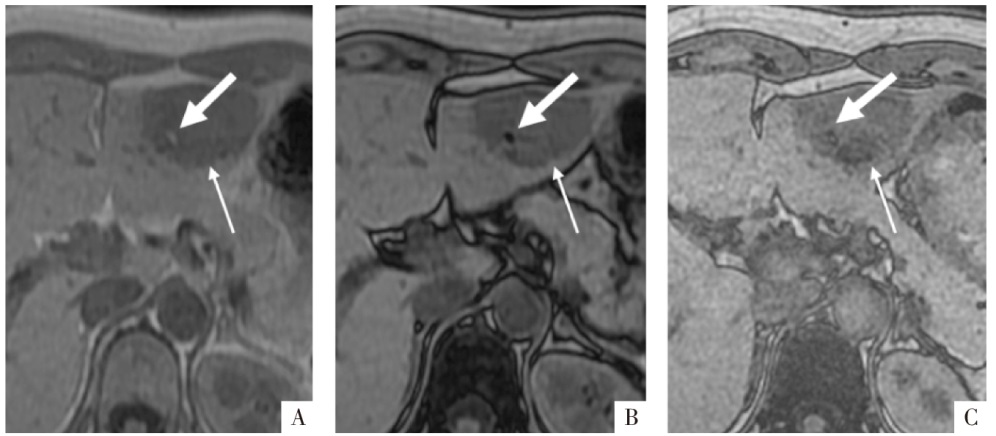

图15

病人女,45岁,含脂滴的肝包虫囊肿。A图,CT 显示肝内2个囊性灶,其中一个囊性灶内见低密度脂滴(白箭);B、C、D图分别为T

1

WI同相位、反相位及水像,相应脂滴T

WI呈高信号,反相位及水像脂滴信号减低(白箭)。